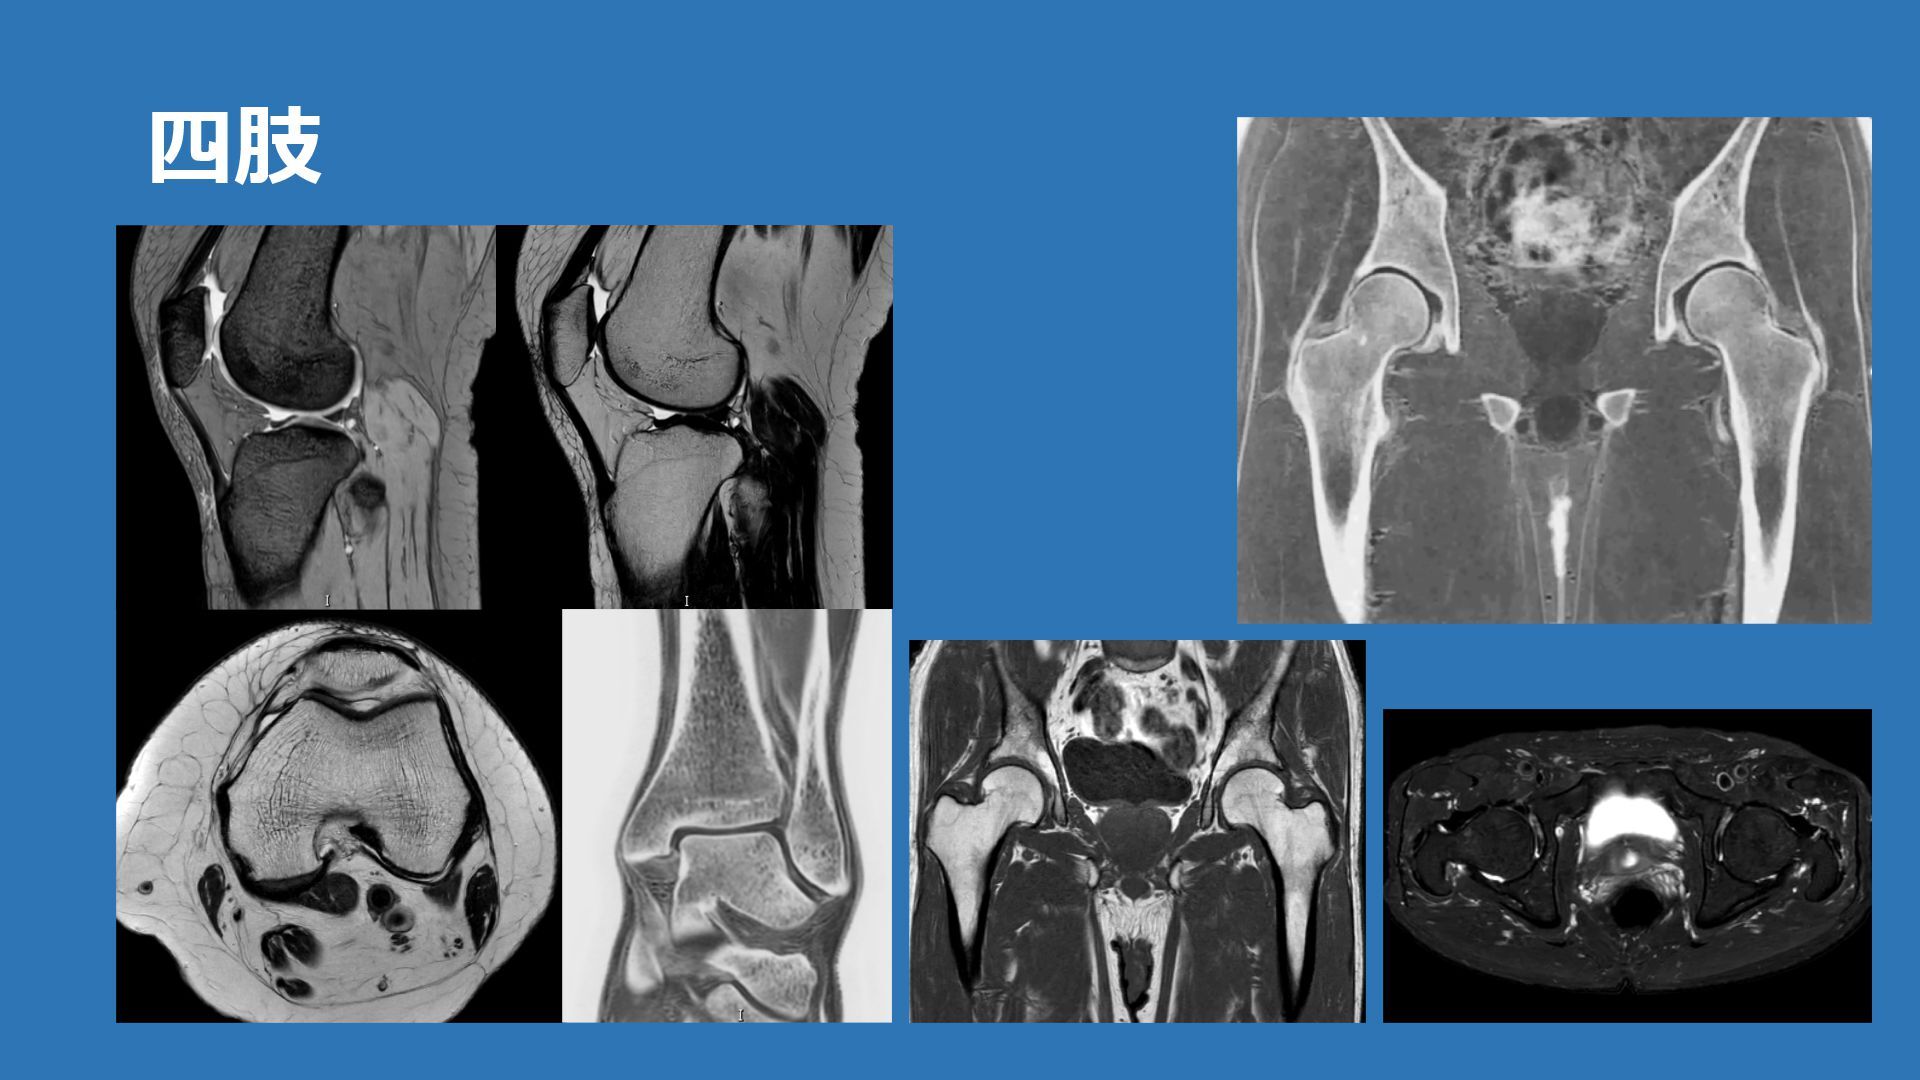

四肢